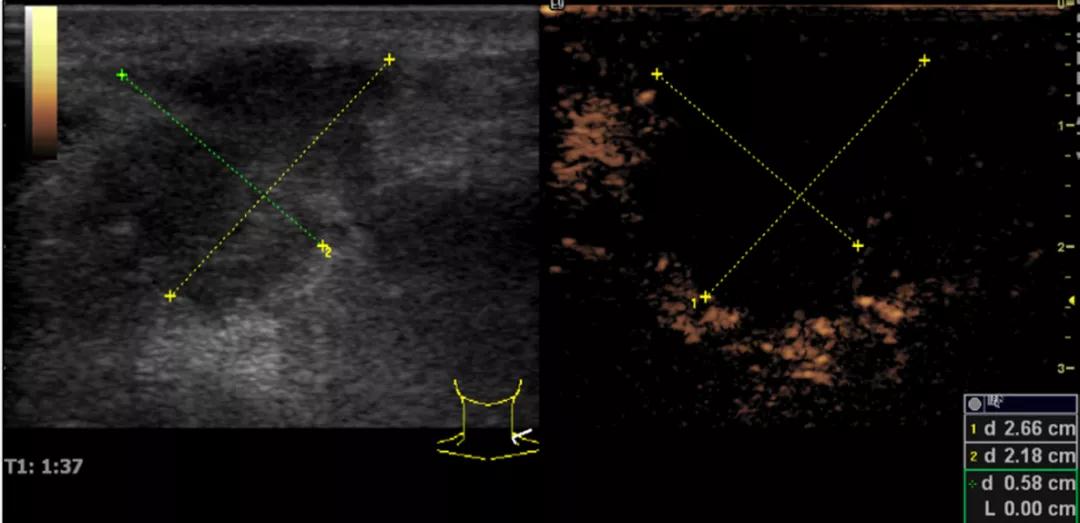

第二例是食管癌患者,术后半年余锁骨上固定淋巴结可触及肿大,疼痛非常明显,系统治疗后无缓解,患者希望通过局部处理缓解症状。造影显示强化信号明显,结节部分区域坏死,故主要针对强化区域从后向前的逐层的消融,皮下进行液体隔离减少烫伤。热消融后影像显示血流增强消失,弹性、硬度增高,一个月后复查显示充盈缺损,完全消融,疗效远超预期。

(病例2图例)